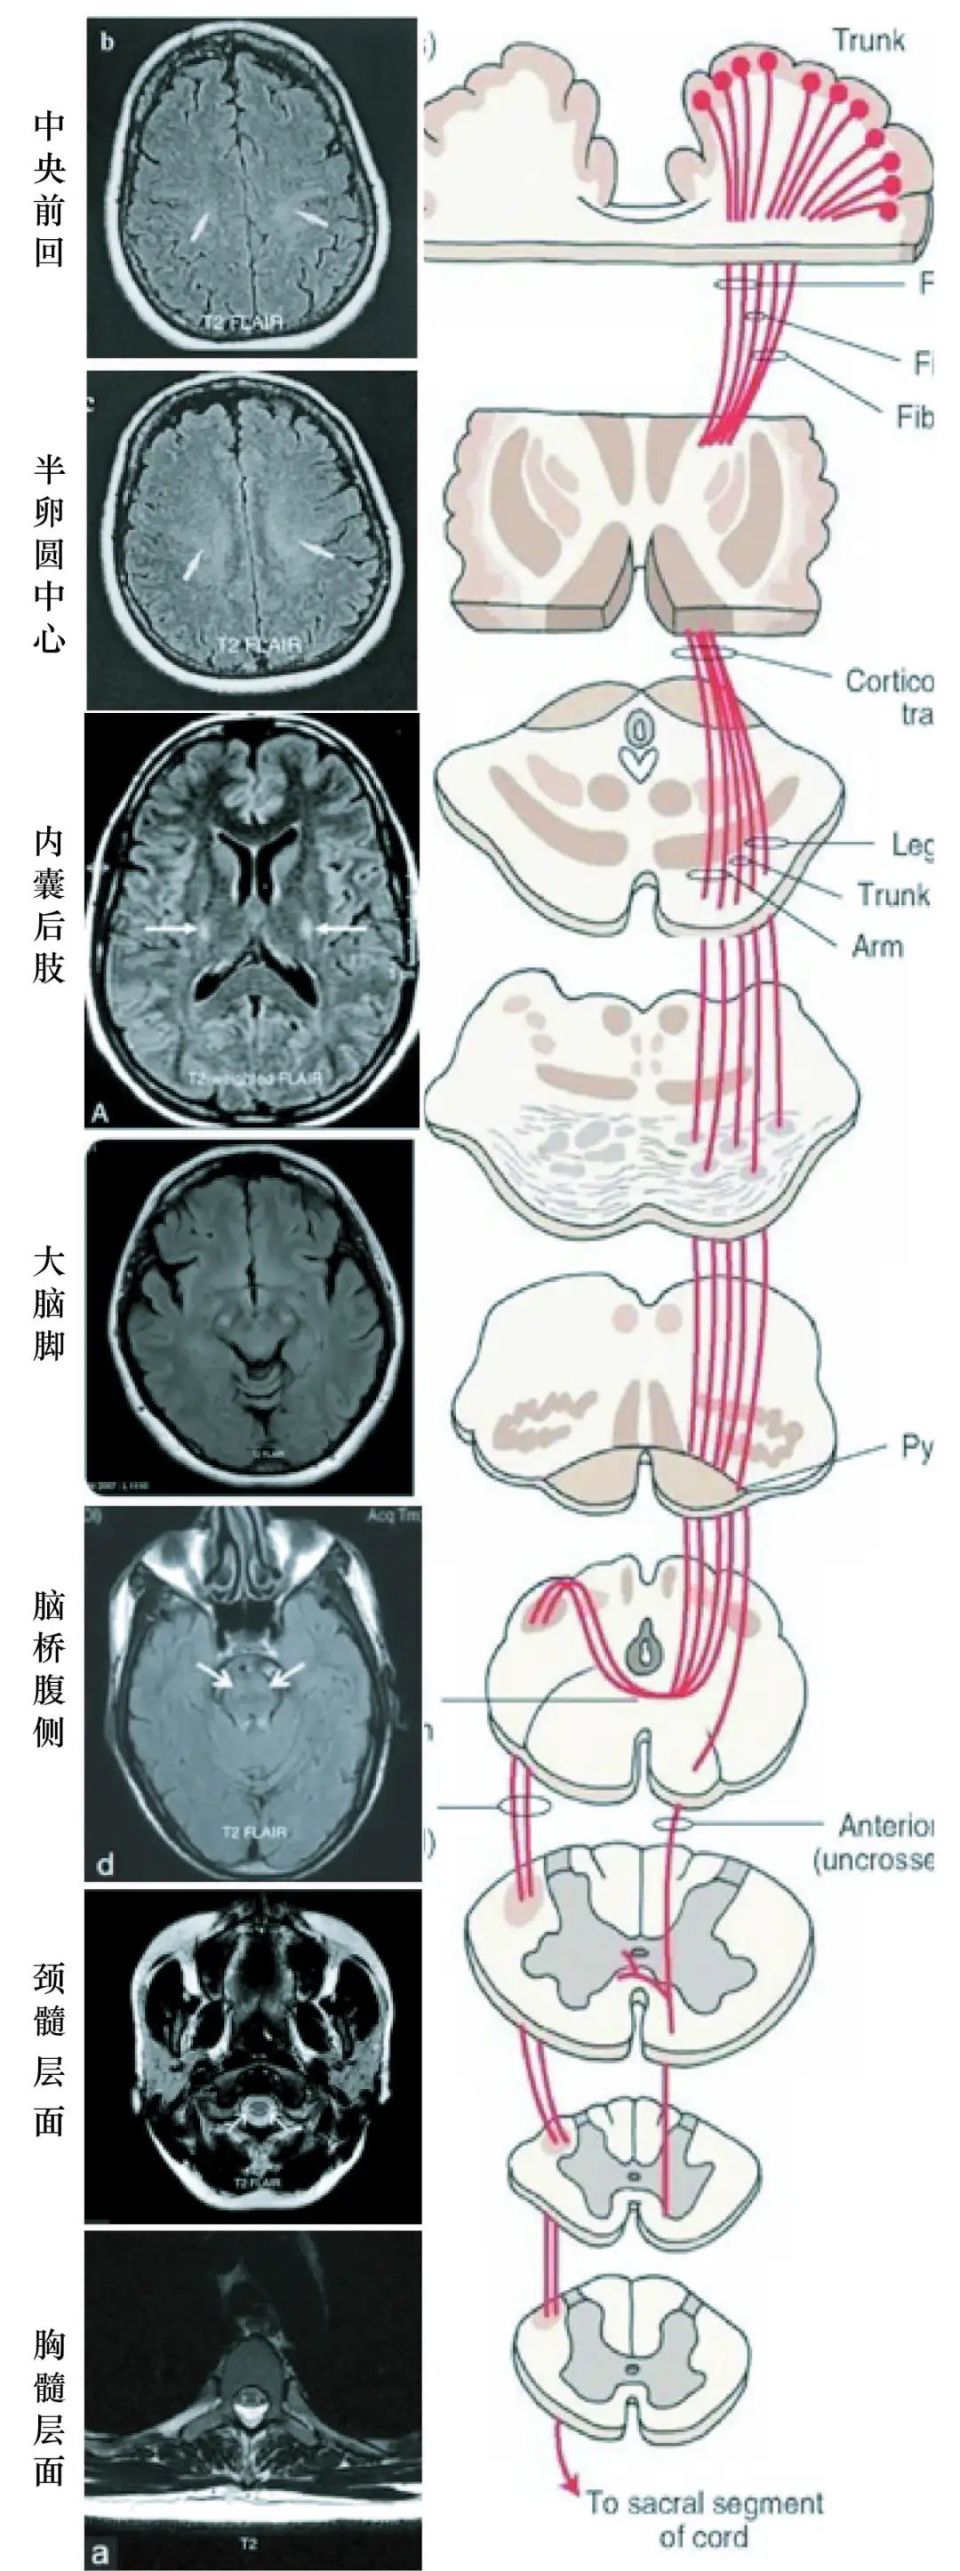

从临床实践的角度,我们常从T2/FLAIR上找皮质脊髓束高信号(图1),但在看这些异常信号之前,首先要知道在不同层面对应的CST哪个位置,因此笔者总结了下图供读者参考。但需要说明的是UMN高信号不是每个有UMN症状的患者都会出现,也并不是ALS特异的征象,中央前回FLAIR高信号对ALS的特异性较高(有研究指出高达94%)1, 2;而双侧CST FLAIR高信号在17-70%的有UMN症状的ALS患者中出现,其中在内囊后肢最明显,另外在半卵圆中心及脑干腹侧也常见到(但特异性不如中央前回FLAIR高信号;需注意除了ALS,还可见于缺血性疾病,维生素B12缺乏等,另外在正常人中也可见到CST高信号)1, 2。

图片

图1